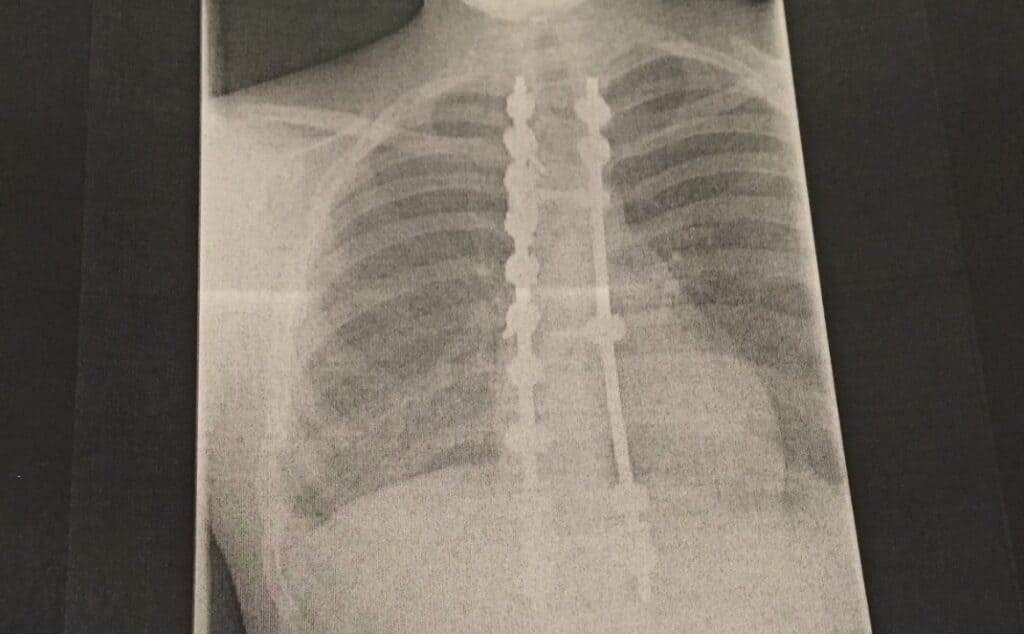

At just 15 years old, Sasha’s world was turned upside down when she was diagnosed with scoliosis. Her spine was curved in three different places and worsening rapidly, leaving her with no choice but to undergo major surgery. Plates and screws were inserted to straighten her spine, and the procedure forced her to stop all physical activity for ten months. For a teenager whose life revolved around judo, the sudden halt was devastating.